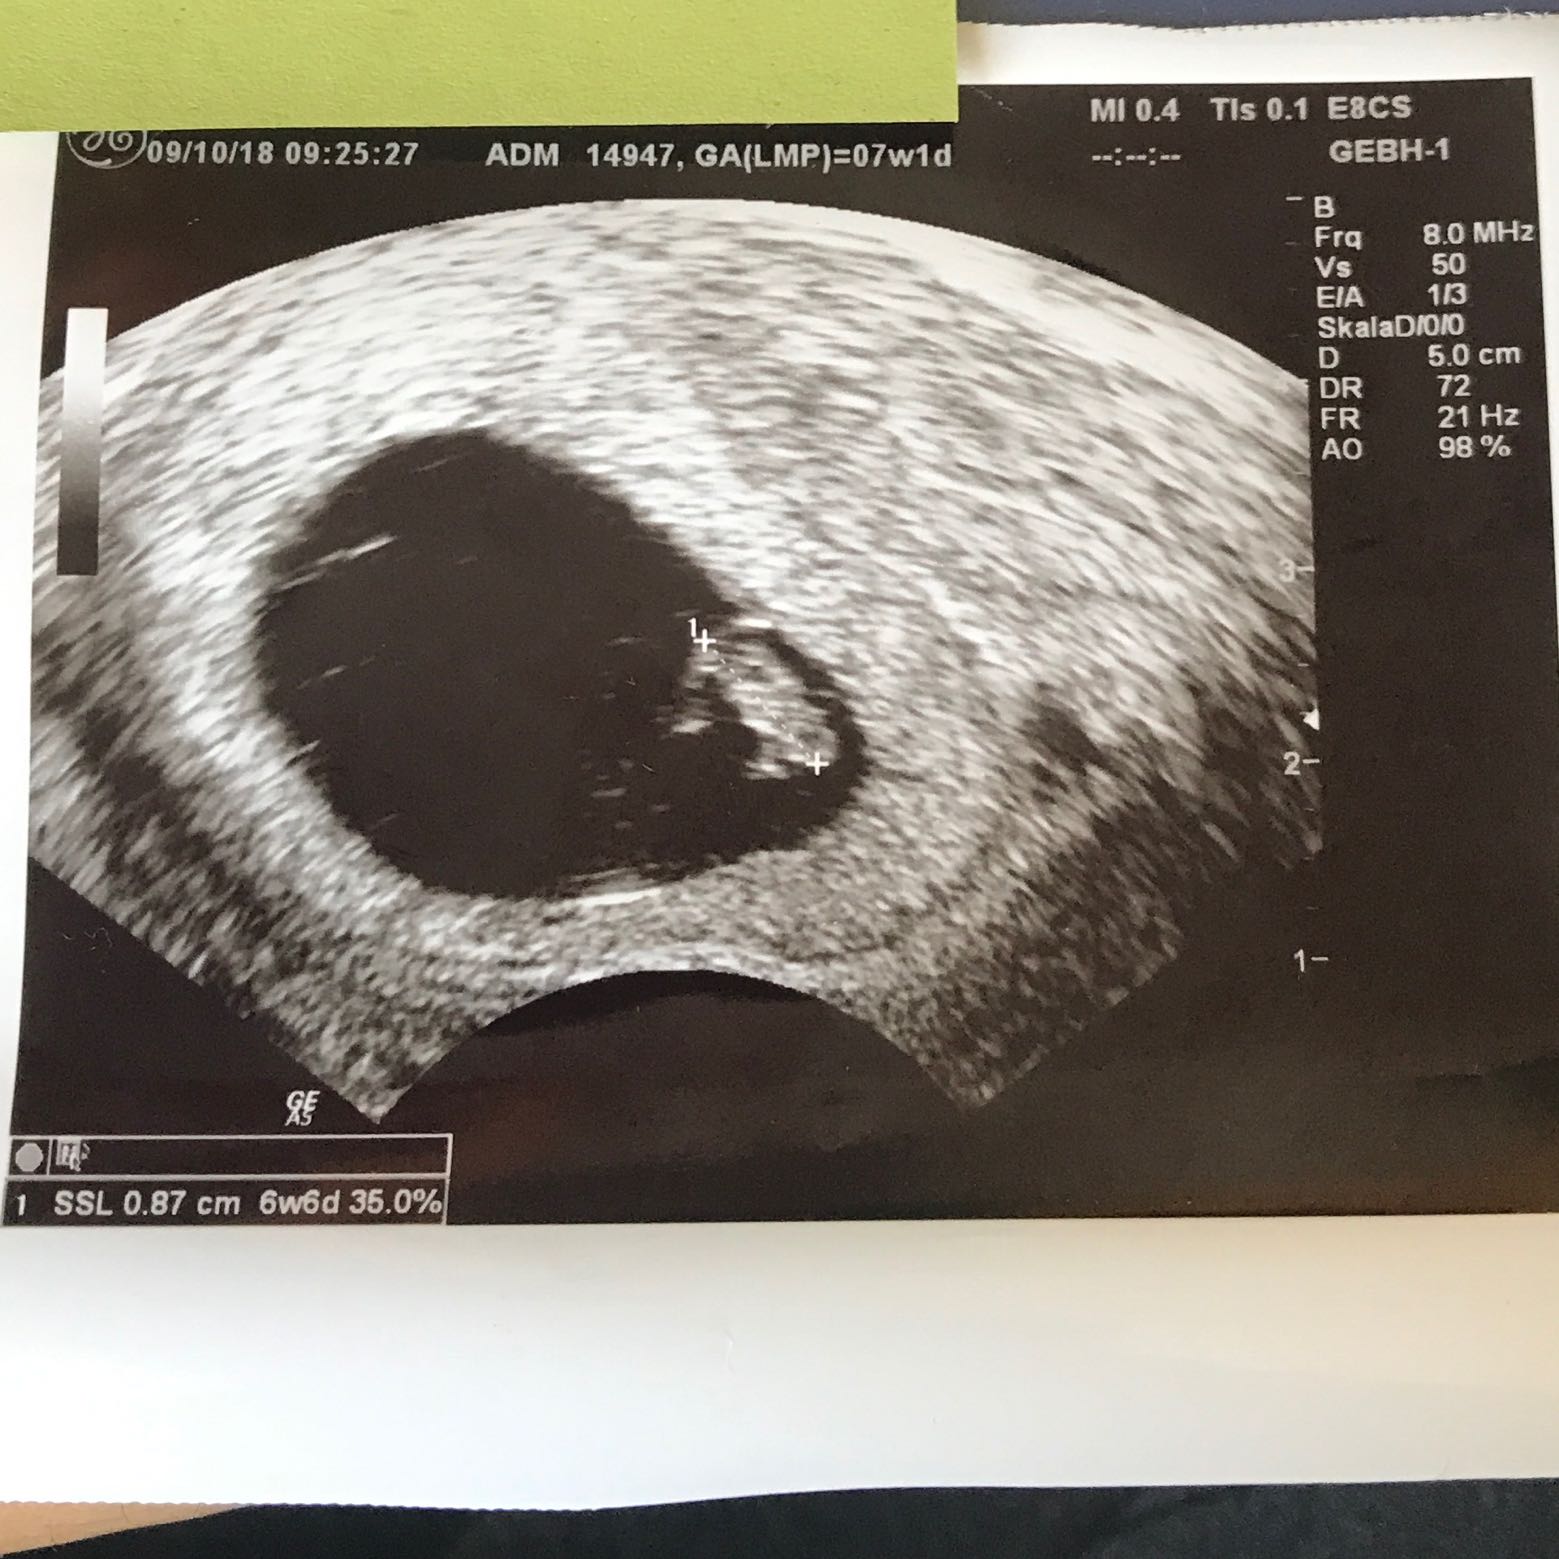

7+5 ssw ultraschall. Ultraschallbild 65 SSW Dieses Bild entspricht dem 5 der 7 Schwangerschaftwoche (65 SSW ) Hier ist der Embryo bereits 8 Millimeter lang und bei einem solchen Bild lässt sich dann auch meist schon sehr gut der Herzschlag sehen. 5 SSW, Ultraschall, Anzeichen, Symptome und weiteres Viele merken in der SSW 5 erst, dass Sie schwanger sind Die Regel ist ausgeblieben und der erste Schwangerschaftstest ist positiv Also heißt erst einmal einen Arzt konsultieren und die Schwangerschaft bestätigen lassen Doch viele haben in der 5 SSW keine Anzeichen einer Schwangerschaft. 7 SSW Entwicklung des Babys Von außen sind noch keine Anzeichen zu erkennen (Sebastian Kaulitzki / Fotoliacom) In der 7 Schwangerschaftswoche ist der Embryo 5–8 mm groß und wiegt in etwa ein Gramm Die Fruchthöhle ist mit einer Größe von 25 mm schon eindeutig zu sehen Der Kopf wächst in diesen en besonders schnell.

Da er gekrümmt im Bau liegt, wird von nun an bei allen Ultraschalluntersuchungen die „ScheitelSteißLänge“ (SSL) gemessen und in Ihren Mutterpass eingetragen. Auf dem Ultraschall ist zwar noch nicht viel zu erkennen, dennoch wächst dein Baby nun immer schneller Dein Bauch wächst vermutlich genauso, denn die 7 SSW bedeutet für schwangere Mütter meist gesteigerter Appetit und die berüchtigten Schwangerschaftsgelüste. SSW kann der Arzt durch Ultraschall erstmals das Geschlecht des Kindes bestimmen Der Körper ist von jetzt an bis kurz vor der Geburt durch das LanugoHaar sowie die sogenannte Käseschmiere (Vemix Caseosa) bedeckt, die eine Aufweichung der Haut durch das Fruchtwasser verhindern und das Baby ausserdem vor Druck, Schall oder Vibrationen schützen.

7 SSW Ultraschall in der 7 Schwangerschaftswoche Die Entwicklung Deines Kindes schreitet nun immer schneller voran Mittlerweile misst das kleine Baby zwischen 2,5 und 7 Millimeter Größere Organe sowie Gehirn und Rückenmark bilden sich Sein Kopf ist im Vergleich zum Körper in der 7. Das Ultraschallbild wurde bei 6 4 SSW aufgenommen Zu diesem Zeitpunkt, also etwa Mitte der 7 SSW, misst der Embryo 6,5 Millimeter Bis zum Ende der Woche wird er noch etwas wachsen und ist dann schon fast einen Zentimeter groß – er ist dann also ungefähr so groß wie eine Blaubeere. SSW 7 Das Babys misst etwa 6mm Alles über den Mutterpass Papa und die Schwangerschaftshormone Alle Infos zur 7 Schwangerschaftswoche gibt es hier.